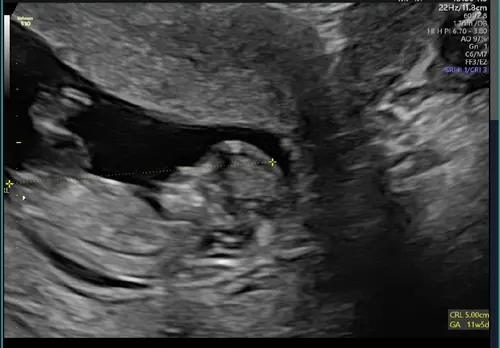

8w 🤩

11w5d vandaag. Baby was zeer beweeglijk tijdens de echo. Zo mooi en magisch om te zien ✨